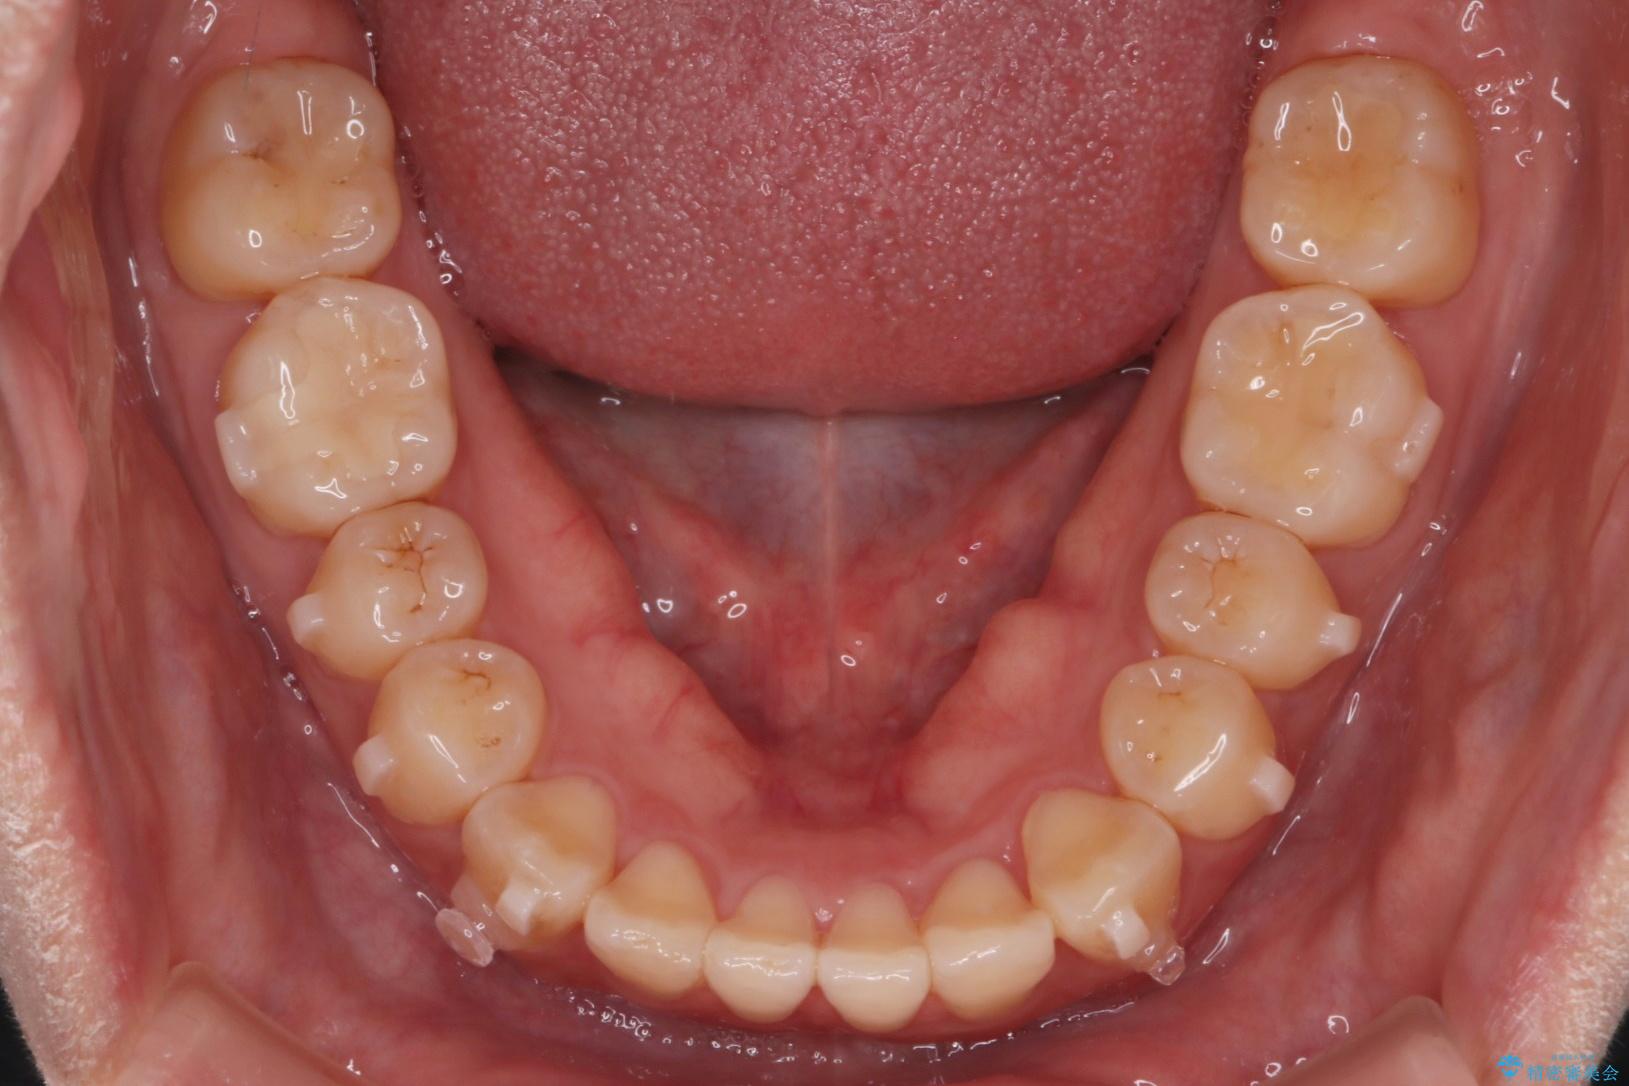

上の前歯のねじれが気になるとご来院された患者様です。

前歯の捻れとがたつきを改善するために、IPR(歯と歯の間を削る処置)と歯列拡大をすることで歯並びを整えていく治療計画を立てました。